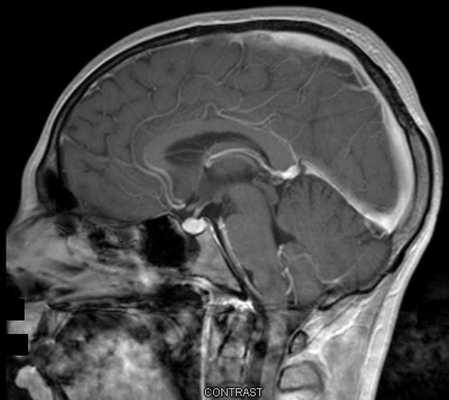

МРТ гипофиза до и после операции по удалению макроаденомы гипофиза